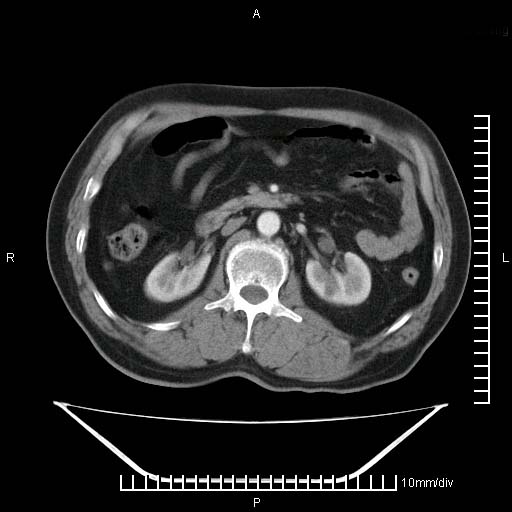

标题: CT25082:肝脏增强:男性,70岁 [打印本页]

标题: CT25082:肝脏增强:男性,70岁

患者以心脏疾病收住院,腹部无明显症状,b超查肝脏有占位。

增强效果不理想。考虑转移,胆囊壁明显增厚,不排除胆囊癌肝转移。

病灶无强化,考虑囊肿。

牛眼征,中心坏死无强化,外缘强化,最外缘又见低密度,考虑转移,与脓肿鉴别

肝内多发转移瘤,右下肺炎症并少量胸水。胃壁增厚建议胃镜,胰尾部“病变”为肠管。

1)肝脏多发性转移瘤(不排除胰尾癌转移所致可能)。2)腹水。3)右侧少量胸腔积液。

ct25082 结果:转移瘤

外院mr结果:胰尾恶性占位。